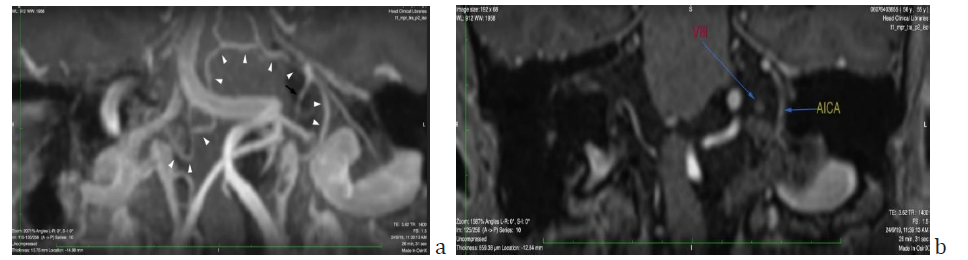

Figure 4: a) Oblique coronal view maximum intensity projection (MIP) reformatted T1-mpr-p2-iso MRI sequence showing the right vertebral artery crossing beneath the left dominant vertebral artery to merge in the left cerebellopontine angle and form the basilar artery, the first part of which is practically horizontal and then turns abruptly upwards at the right lateral border of the clivus. Right and left AICAs are marked with white arrowheads. The left AICA emerges with a paradoxically vertical proximal end, curves smoothly and then splits into the labyrinthine (black arrow), medial and lateral cerebellar branch. Anastomosing branches with other pontine arteries are evident b) Note the anatomical relationship of the VIIIth nerve with the labyrinthine branch of the AICA pictured in a.

According to Smoker’s criteria BA reaches the lateral border of the clivus (Laterality criterion grade 2) (Figure 3b). The level of bifurcation reaches the floor of the third ventricle (grade 2). The dimension of the BA at the midpons level is 5.12mm. (Smoker’s criteria for ectasia >4.5mm). In the present case the vertebrobasilar system is tortuous and elongated with moderate ectasia. No signs of intraluminal thrombi are found. There is a mass effect on the brainstem and a dominance of the left vertebral artery (side to side difference of vertebral artery diameters was >0.3mm) [7] (Figure 3a).

Things get even more complicated as in studies with large samples of patients with SSNHL and posterior circulation anatomical variations (VBD, vascular loop) Maruyama et al. [6] found no correlation between the laterality of the above configurations of the arteries and the affected side, whereas Kim et al. [18] found the laterality of BA curvature and laterality of SSNHL to be inversely associated in a population sample in which right sided BA curvature and left sided hearing loss prevailed. They used modified Smoker criteria which was not the case in the study of Maruyama et al. [6] who simply mentioned the existence of BA curvature without grading it. Our patient fulfilled the Smoker criteria of a markedly tortuous BA (Smoker laterality 2) and coincided with Kim’s findings of a right sided BA curvature and left sided hearing loss. Additionally, he had a severely tortuous VA causing the mass effects on the brainstem (Figure 3a). According to Kim et al. [18] SSNHL can be due to blood circulation disturbances in a stretched AICA deriving from a basilar artery which is curving contralaterally. Sunwoo [19] sustains the same hypothesis as in his study the severity of BA tortuosity correlated with occurrence of severe sudden hearing loss on the opposite side. Moreover, the pathomechanism of low wall sheer stress in the inner wall of a curved basilar artery and traction of the pontine perforators leading to formation of microthrombi is a possible explanation of the fact that pontine infarctions are more frequent on the side contralateral to BA curvature [20].

In the present case the left AICA emanates in a direction perpendicular to the typical horizontal one, which could be a factor leading to blood flow disturbances. However as seen in Figure 4a the presence of anastomoses with neighboring pontine vessels, as described by the cadaveric study of Nishijima [21] could be a possible reason that a major ischemic event has not taken place. To what extent such a vascular configuration could be responsible for a moderate cochlear ischemia leading to a moderate hearing loss in a limited area of the cochlea, is highly speculative.